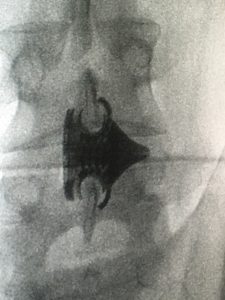

Innovation at Tsunami Medical comes in various shapes and forms, but they are typically small and incredibly complex. The company’s latest innovation breakthrough – the Giglio Interspinal Fusion System – focuses on developing implants that are almost ready for use, straight from a metal additive manufacturing machine.

Giglio consists of an interspinal spacer device and the necessary tools for its positioning and fixing within a minimally invasive operation. Five mobile, articulated pieces allow for the extraction of the fins for anchorage to the vertebrae.

The surgical operation is performed by making an incision for the passage of the device. This is correctly positioned using a guide wire that is stretched from the insertion point. Once the device has been positioned, it is tightened by a special tool, which is then removed, together with the guide wire.

Here, Tsunami has been able to take advantage of GE Additive’s DMLM technology in a number of innovative ways. DMLM offers the ability to create precise geometries, including gears and mechanical moving parts – on a very small scale – with no assembly needed.